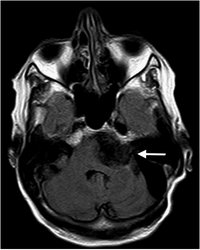

Epidermoid - T1 mit KM - axial

Keine Kontrastmittelaufnahme